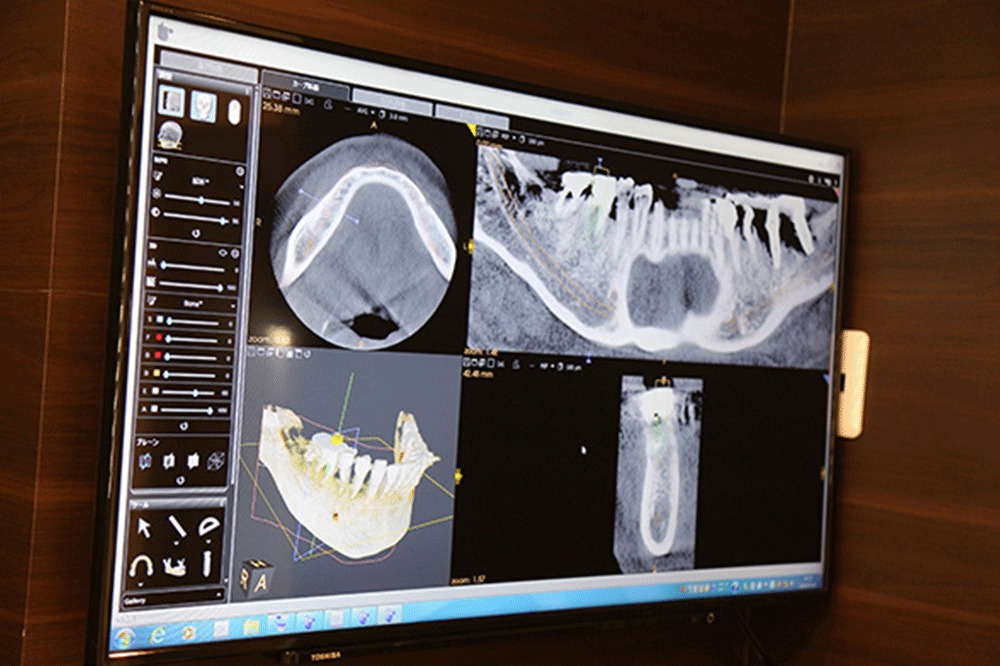

歯科用CT

その名の通り歯科用のCT装置で、骨の状態を立体的に把握できたり、神経や血管の位置などを把握できたりすることができます。インプラント治療において、精密な計画を立案するのに必須の装置といえます。

インプラント術前シミュレーションソフト

CTで撮影したデータをもとに、多角的に各種測定やインプラントの埋入シミュレーションがおこなえるソフトです。